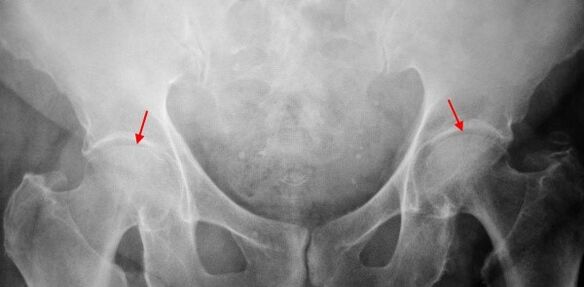

En las imágenes de rayos x para la coxartrosis de segundo grado, se determina el estrechamiento desigual significativo de la brecha articular (más de la mitad desde la altura normal). La cabeza femoral se desplaza un poco hacia arriba, se deforma y aumenta de tamaño, y sus contornos se vuelven desiguales. Los crecimientos óseos con este grado de coxartrosis aparecen no solo en el interno, sino también en el borde exterior del acetábulo y salen del cartílago.

En Coksartrosis 3 grados El dolor se vuelve constante, la preocupación de los pacientes no solo durante el día, sino también por la noche. Caminar es difícil, cuando se mueve, un paciente con cooksartrosis se ve obligado a usar un bastón. El volumen de movimientos en la articulación está muy limitado, los músculos de la nalga, las caderas y las piernas inferiores están atrofiadas. La debilidad de los músculos de extracción del muslo se convierte en la causa de la desviación de la pelvis en el plano delantero y acortando la extremidad en el lado dolorido. Para compensar el acortamiento, un paciente que sufre de cooksartrosis, al caminar, inclina el cuerpo a la dirección dolorida. Debido a esto, el centro de gravedad cambia, la carga en la articulación dolorida aumenta bruscamente.

En las radiografías para la coxartrosis del tercer grado, un estrechamiento agudo de la brecha articular, se detecta una expansión pronunciada de la cabeza del muslo y múltiples crecimientos óseos.